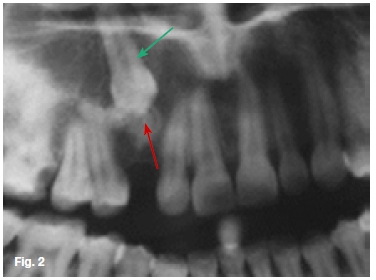

Figure 1 is of a patient with the complaint that her upper right canine has not erupted. The cropped pantomo-graph (Figure 2) shows an impacted canine with an irregular low density lesion at the incisal edge, (red arrow) is very similar to the dentin of the impacted canine (green arrow). A diagnosis of a dentinoma was made. This is an extremely rare tumour of odontogenic origin and occurs predominantly in the mandible and is frequently associated with an impacted tooth. The radio-graphic appearance is not specific, but usually there is a radiolucent area containing a large, solitary opaque mass or smaller masses of calcified material. Figure 3 is a cropped pantomograph of a fourteen year old female presenting with a swelling in the 42-35 region. A mixed radiolucent/radiopacity lesion causing displacement of left mandibular canine and first premolar is discernible. A histological diagnosis of ameloblastic fibro-dentinoma (AFD) was made. The AFD is a rare mixed odontogenic tumour composed of odontogenic epithelium, immature connective tissue and characterized by the formation of dysplastic dentin (ye ow). It is slow growing, is often an asymptomatic lesion with a predilection for males. Radiologically, it shows unilocular or multilocular radiolu-cency with or without radio-opaque areas. Histologically, it is similar to ameloblastic fibroma but also shows dentin formation. Figure 4 is an oblique lateral radiograph of a Ave year old male with a slow growing swelling in the premolar/molar region of the left mandible causing expansion and disturbance of eruption of the teeth in the region. Radiographically the lesion is characterized by a well-defined radiolucency containing several small, irregular fragments of tooth material (white arrow). A histological diagnosis of an ameloblastic fibro-odon-toma (AFO) was made. The lesion is very similar to the AFD, and consists of soft tissue, odontogenic epithelium, enamel and dentin. Occasionally the tumour is discovered during routine dental radiographic examination